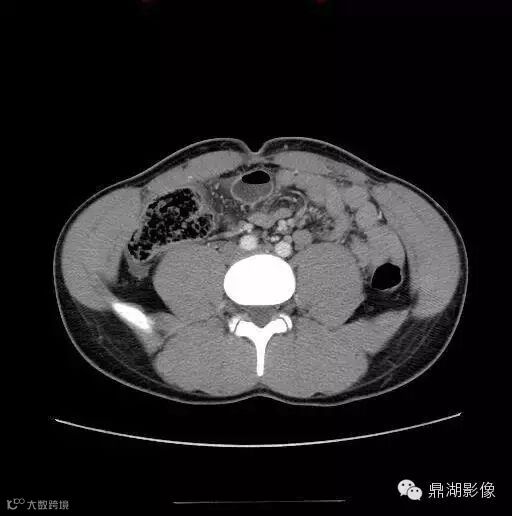

18岁男性,腹痛,定位模糊,无直肠出血。

影像学描述

诊断

Meckel憩室炎 Meckel's diverticulitis

典型的位置位于下腹部(少数盆腔内)中线附近(67%),尤其是肚脐附近是其典型位置,病变与肚脐关系密切尤其是可见纤维索相连高度提示为Meckel's 憩室炎。发生于回肠肠系膜对侧,距回盲瓣50-60cm以内。

肠系膜炎性改变常较显著,表现为系膜密度增高及周围脂肪内条索状影,部分可伴腹水。

憩室壁常增厚,增强后绝大多数可见粘膜面强化。